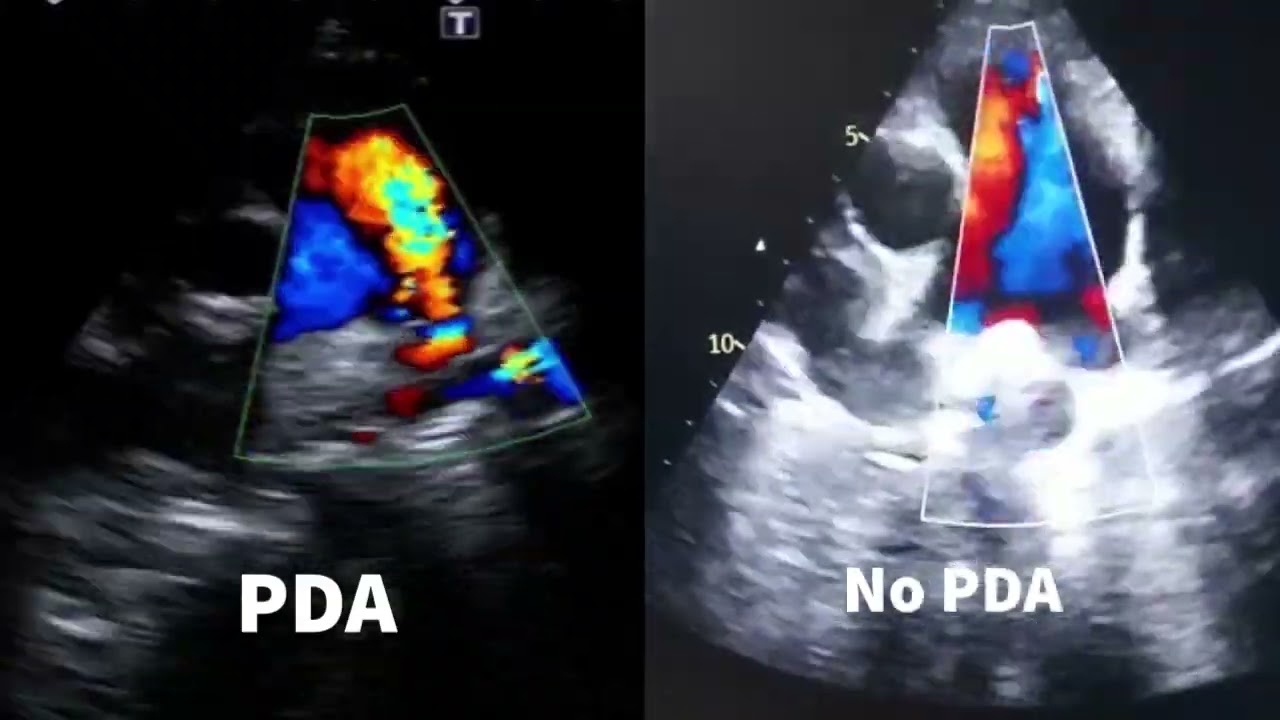

mais elas vermelhos para carregar mas oxigênio e a gente começa a ter policitemia tá então aí a gente tem um prognóstico bem pior o certo é o diagnóstico o diagnóstico definitivo é obtido através do exame ecocardiográfico transtorácico que é o que a gente faz né pastor aspecto digitado errado aqui enfim dá um desconto e o esofagico tá E também pela angiografia né um cateterismo o que a gente faz muito menos isso para fazer os diagnósticos na rotina nosso cardiológica ela eco eco eco eco o dia inteiro Todo dia e a gente vai pegar no transtorácico

tal e E então comecei pela via de saída né Achei bem normal o ato Aparecida um pouquinho de homem realmente né Com relação à horta aqui na via de saída Ok mas não me chamou muita atenção a Carol tinha visto aumente deatro também no exame dela quando eu me disse vão ver Não Acabou que nem deu aumento aí fui aí primeira coisa que me chamou atenção foi a insuficiência pulmonar amor tem paciente que tem às vezes fisiológicas vezes já nasce com muita ciência sim mas é uma extensão maior lona aqui né e o diâmetro da

artéria pulmonar também tava esquisito e tá vendo tinham é uma turbulência aqui ó essa turbulência dentro da artéria com o ar me chamou atenção de cara Carol também viu isso ela viu que tinha alguma coisa estranha com fluxo pulmonar aí é mais uma foto né da Justiça pulmonar E aí você também passar pros vídeos aqui no vídeo depois aí eu tirei uma foto do fluxo pulmonar nas estude né do VD eu vi que dava para ver o filme Ok mas aí tem alguma coisa vermelhinha saindo daqui do fundo tá vendo o que fazer uma turbulência

do lado desse lado aqui da artéria aí tem alguma coisa errada aí a seguir o exame aí eu falei já pus a pergunta que será que é um PDA não tá a característica que não uma um jato continuo mas eu via toda hora alguma coisa turbilhando aqui e não era o achei isso é pulmonar e não era uma estenose pulmonar Porque daí eu eu fiz eu peguei e essa imagem aqui ó e diz que pus a amostra para registrar o fluxo ar bem no cantinho da artéria aqui no lado esquerdo da minha tela é e

tenta tentando fugir da da turbulência aí ó pois bem do que eu tinha consegui pegar o fluxo pulmonar razoavelmente preciso tá um pouco alto Ok mas não é uma estenose pulmonar é bom presta alto aqui pode ter uma sobrecarga de volume né pensei ser um PDA vai ter sobrecarga de volume vamos lá aqui tem um vídeo não dá para ver muito bem à insuficiência pulmonar né e eu vejo eu já tinha vermelhinha aqui ó hoje novo a China que na hora da Sister ele aparece mais fácil né mas ele ele via de regra ele tá

quase toda vez mas ele é mais intenso Em algum momento e menos intenso em outro E aí ele acompanha adiasse ver que o aí vocês pulmonar e na diástole também é mais visível né de Astro vai ter mais um vídeo aqui e eu sem querer que eu vou ver E aí tem momento que é muito ó viu é muito caro por isso que já pegou um PDA e vice já tô aqui vermelho turbulento para cima que muito facilmente eu vi aí ficou bem mais jovem para mim eu já tinha saindo daqui bem na seta do

meu mouse aqui ó dá para ver eu já tinha vermelhinho saindo aqui ó você vê que ele não tem a ver com fluxo pulmonar ele é muito mais forte nade ar na sístole né quando da contração ele também aparece mais mas ele persiste durante a diástole de novo pode ver ele persiste junto no mesmo momento que é insuficiência pulmonares está acontecendo Então ele tava assistindo na diástole falei bom aqui eu já não tive muita dúvida que era um pedaço aí eu esperava algumas confirmações durante primeiro a turbulência né tentei registrar aqui aí eu coloquei o

eu não estava convencido que o átrio o ato não tava tão aumentado EA insuficiência da me troca Carol tinha visto nos vídeos dela Era exatamente o que eu via era mas você ser pequena eu falei não não tem alguma coisa errada aí tem aquela turbulência na artéria pulmonar e tal aí nós marcamos a reavaliação porque não tava batendo é só bater o raciocínio depois que a gente começou a olhar de novo aqui eu mudei um pouco a configuração do Collor dá para ver melhor eu já to subindo aqui em amarelo vendo e ele vai diminuir

a eles vai de novo forte vai diminuindo de mais forte é porque a pressão tá mais perto de equalizar óleo J vermelho aqui bem na base aqui da artéria pulmonar eu já tô bem sim eu não consigo pausar e esse jato aqui ó Tá eu já to subindo aqui nesse momento tá vendo que é que tá na diastro eu tenho esquecido pulmonar aqui também certo É mas o vídeo que te ver e eu tô com um pouco de artefatos aqui no colo né mas eu tô tentando pegar o jato bem mais evidenciar mais o jato

o ok toda essa área aqui ó a laranja eu já to subindo tá e o fluxo Azul das histórias a da artéria pulmonar descendo tá é bem comum a gente ver isso quando é um pedal mais novo dizer assim os olhos já estão aqui ó vermelhão subindo aqui aqui na diástole também a de Aço eu vi é bem melhor porque não tem as isso não tem aquele Jato da artéria pulmonar descendo né é bem mais fácil de ver um PDA quando você tá com ele mais novo 10 assim ó se alguém alguém com a dúvida

aí Não não é tipo Renan oi oi e é eu acho que assim eu te fiz vários vídeos né do acumular também foi o que mais me chamou atenção só que não passou na nossa cabeça de imediato um cão de 4 anos estava com pedal né exatamente e sem sintomas a quer dizer tinha sintomas de cansaço então é o que chamou atenção foi a dilatação estava tentando encontrar uma razão para isso mas como ele não tá nítido é que você não é eu não tive tempo de procurar os outros pedaços que eu já peguei é

muito fácil de ver super nisto Adriana tá aí se puder dar uma opinião dela também quando ela desce pega algum é muito nítido mas nesse caso não tava neste essa turbulência né Aí eu comecei a juntar os pontos só ali na hora né que eu fui pensando e aí realmente que me lembrou foi há quatro anos não é para ter generado ainda não é um cara não é um Charles Cavalier King Spaniel que faz da geração de válvula Ah sim também não tinha insuficiência de mitral para isso Adriana também falou Alguns são fáceis de ver